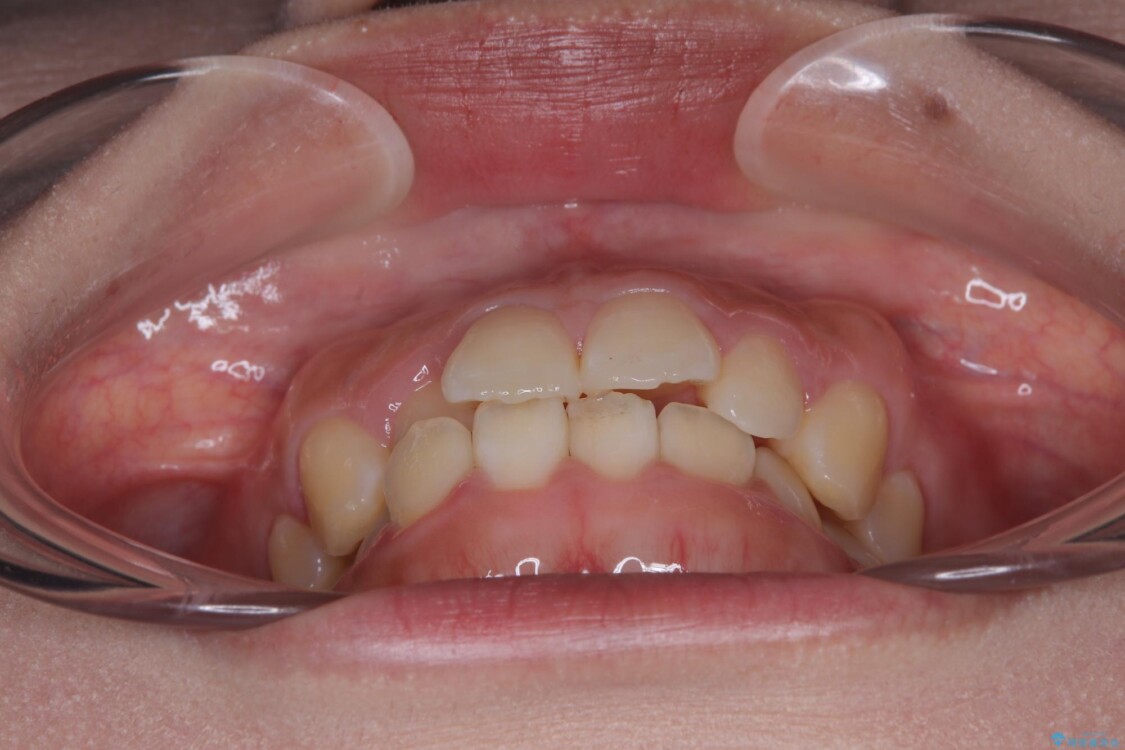

前歯のデコボコが気になるでのことで来院された患者様です。

歯列アーチが狭くスペース不足により前歯がデコボコしている状態でした。見た目を改善しつつ、前歯を前方に突出させず、自然な笑顔を目指したいというご希望でした。

治療前

• 目立ちにくい表側装置で1年完了!狭いアーチを側方拡大し前歯のデコボコを整えた症例 治療前画像